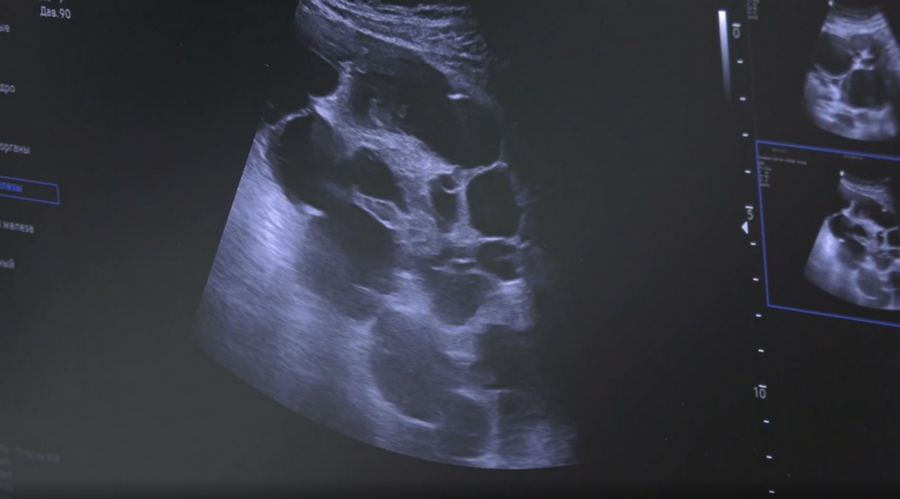

На мониторе ещё один снимок, но сделанный 67-летней пациентке, которая долгое время наблюдалась с кистой яичника. В этот раз специалисты центра обнаружили у неё образование.

«Мы не можем сказать по картинке УЗИ, имеем ли мы раковое заболевание на сегодняшний момент или это доброкачественное образование. Но вероятность злокачественного образования здесь больше 50%. Эта пациентка требует дальнейшего дообследования», — комментирует результаты обследования пожилой жительницы Мурманска акушер-гинеколог Юлия Рагозина.